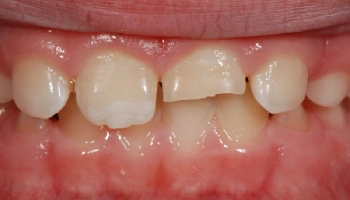

Trauma: Central Incisor veneers

Before and after images of central incisor veneers. Before and after images of central incisor veneers.